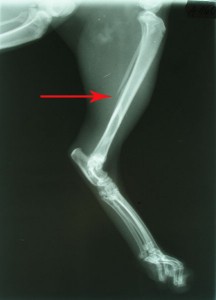

Rentgeny zlomené kosti holení a lýtkové